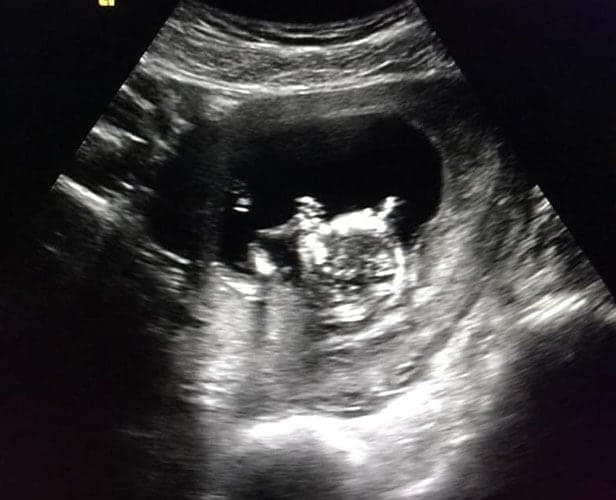

Ultraschallbilder aus dem 1. Trimester (1. SSW bis 12. SSW)

Im ersten Trimester sind die Ultraschallbilder meist noch schwer zu deuten. Oft erkennt man in den letzen Wochen des ersten Trimesters gut den Körper, den Kopf und die Gliedmaße. Das Geschlecht kann man in dieser Zeit meist noch nicht erkennen.